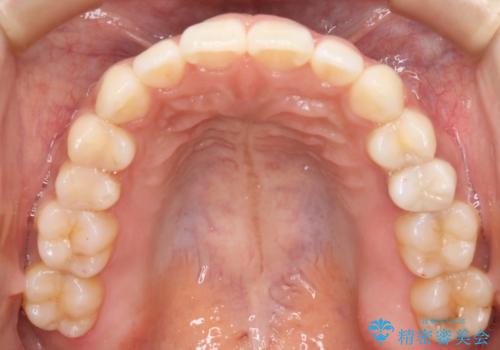

- インビザラインで全体矯正を進めてきましたが、装置の特性上右上2番目の歯の捻じれがなかなか治らず、シミュレーションを作り直すタイミングが来ました。

患者様と相談の上、短期間で確実な効果が得られるワイヤー部分矯正を取り入れて治療を進めることとしました。

丸みがあり掴みどころのない歯や大きい歯に挟まれた小さい歯は物理的にマウスピースの力が作用しにくく、作成したシミュレーションと実際の動きがズレることが良くあります。

こうした際に効率よく修正を行うには、歯に直接装置を張り付けて矯正力を伝えることのできるワイヤー装置を部分的に使うことが有効となります。

マウスピースはシミュレーションを作り直すことができるのが特徴ではありますが、苦手な動きは何度シミュレーションを作り直してもうまく動き切らないことも多いため、時間と費用を無駄にしないためにも思い切ってワイヤーへの切り替えを選択することも必要といえます。